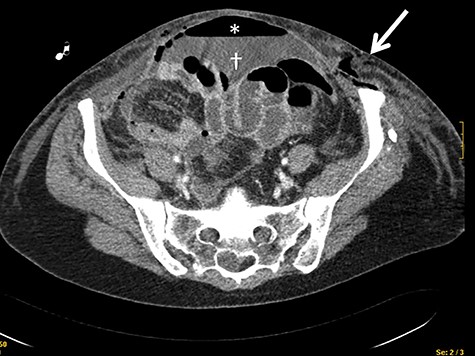

A 43-year-old woman with multiple drug allergies (streptomycin, tetracycline and metamizole) required laparoscopic right oophorectomy for incidental ovarian cyst. 48 Hours after the operation, she complained of diffuse left abdominal pain and tachycardia and hypotension were documented and tachycardia and hypotension, requiring vasoactive drugs. Physical exam revealed a diffuse cellulitis on the left abdominal wall that rapidly spread to the vagina a rapid caudal extension to the vagina. CT scan showed pneumoperitoneum and thickening of the abdominal wall in the left flank (Fig. 1). She went to the OR, the exploratory laparotomy demonstrated diffuse fecal peritonitis with two small bowel perforations, requiring primary repair with surgical suturing and without small bowel resection. Empirical antibiotic treatment with meropenem an cliindamycin was started.

CT scan showing the presence of air in the abdominal wall (arrow) and pneumoperitoneum (asterisks) and intrabdominal liquid (dagger).